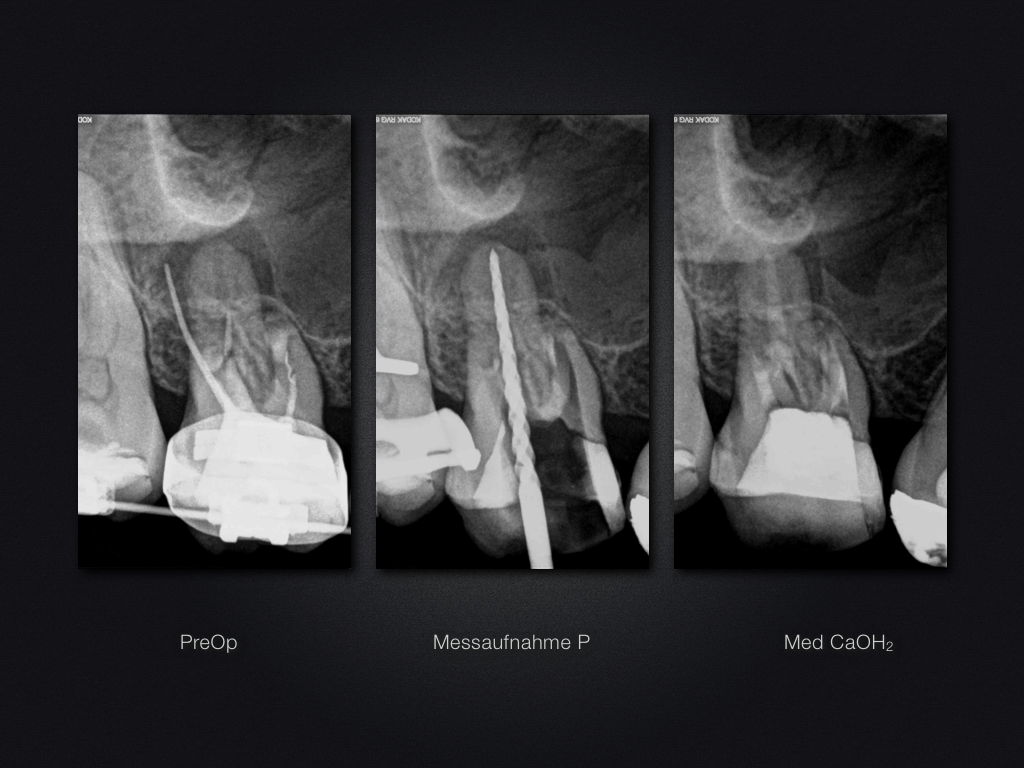

16D.012

Saving Hopeless Teeth (XXX)